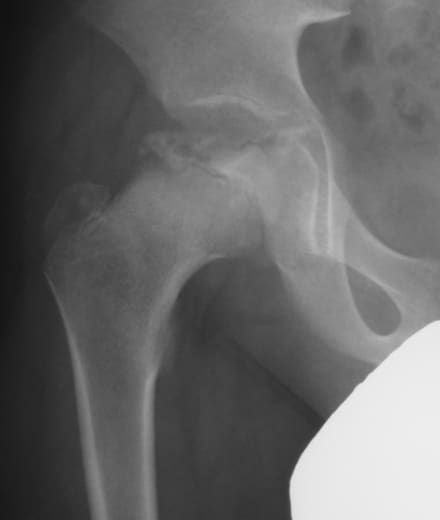

2. 低学年の活発な子に忍び寄る「ペルテス病」

もう一つ、4歳〜10歳くらいの活発な男の子に多いのが「ペルテス病」です。

- どんな病気?: 股関節の「頭」に血が通わなくなり、骨が壊死(えし)して潰れてしまう病気です。

- 見逃せないサイン: 運動した後に足を引きずる、股関節が硬くてあぐらがかけない、といった症状がじわじわと現れます。

「子供だからすぐに治るだろう」と放っておくと、骨が変形したまま固まってしまい、若いうちから「変形性股関節症」に苦しむことになってしまいます。